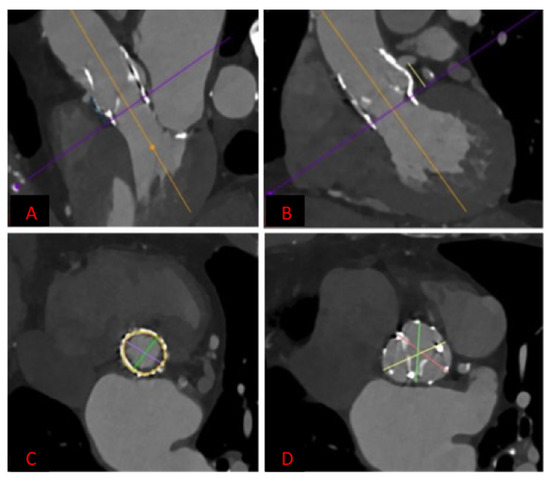

2.2. Technology

2.3. VIV-TAVR Planning and Technical Procedures